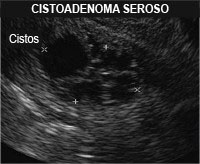

Neoplasia Cística Serosa – Cistoadenoma Seroso

Tumor cístico (líquido em seu interior) tipicamente benigno composto de uma única camada de células epiteliais cuboides contendo glicogênio. Tem correspondido a cerca de 14% das lesões císticas achadas no pâncreas incidentalmente. Raramente se malignizam para cistoadenocarcinoma com risco de 3%.

Aparece na Ressonância ou tomografia:

- lesão cística com liquido em seu interior de baixa densidade associado a septações;

- calcificação central estrelada (“Star Calcification” ou “Surnbust calcification”) ou ainda pequenos cistos conjuntos dando um aspecto em colmeia (“Honneycomb”) ou esponja (“Sponge”).

- raramente há a presença de um cisto único com parede fina chamado cistoadenoma oligocístico-macrocístico. Nos casos inconclusivos deve ser realizada a eco-endoscopia realizando biópsia da parede do cisto e dosagem de substâncias do líquido aspirado;

- células e liquido ricos em glicogênio, se atipias (células não-cancerígenas);

- tem valores baixos de marcadores tumorais como CEA(abaixo de 5), CA 19,9 (abaixo de 37,0) ,amilase normal.